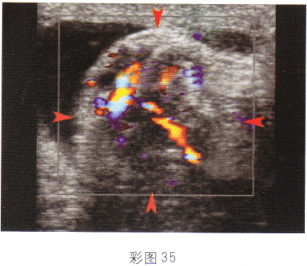

4.女性,27岁,停经48天,阴道不规则出血6天;血HCG70μg/ml。结合超声图像(彩图37),最可能的诊断是

A.卵巢畸胎瘤

B.附件炎性包块

C.子宫浆膜下肌瘤

D.异位妊娠

E.卵巢囊腺瘤

正确答案:D解题思路:附件区见囊实混合性光团,边界尚清晰,子宫腔内有分离。患者有停经,不规则阴道出血,且血HCG增高。